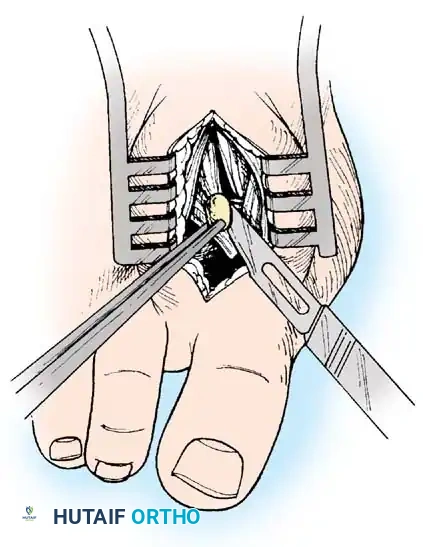

FIBULAR SESAMOIDECTOMY: PLANTAR APPROACH

• If a plantar approach (Fig. 78-21A) is chosen for fi bular sesamoidectomy, have an assistant hold the ankle dorsifl exed, and use a headlight for seeing into the full depth of the wound. Avoid the fl exor hallucis longus tendon and the neurovascular bundle to the fi rst web space.

• Flex and extend the hallux, and inspect the radiograph to locate the sesamoid. Beginning 1 to 1.5 cm distal to the metatarsophalangeal joint, make a longitudinal incision in the plantar surface of the foot, extending the incision proximally 3.5 to 4 cm between the fi rst and second metatarsals.

• If the fi bular sesamoid requires excision, it usually is subluxed.

• When the skin and fascial septa within the forefoot pad have been separated, insert a small self-retaining retractor.

• Using small, blunt-tip dissecting scissors, identify the neurovascular bundle to the fi rst web space, and retract it laterally or medially, depending on the position of the sesamoid (Fig. 78-21B).

• Palpate the sesamoids, and fl ex and extend the hallux to locate the fl exor hallucis longus tendon.

• Open the pulley over the fl exor hallucis longus tendon, and retract the tendon medially. This maneuver is made easier by having an assistant hold the foot in dorsifl exion at the arch with one hand and fl ex the metatarsophalangeal joint to relax the fl exor hallucis longus tendon with the opposite hand.

• At this point, the intersesamoid ligament should come into view; divide it completely (Fig. 78-21C). This may require moving the scalpel 1 or 2 mm laterally or medially to fi nd the groove between the sesamoids.

• Incise the cleavage plane between the two sesamoids, while retracting the fl exor hallucis longus muscle medially and the neurovascular bundle laterally.

• Grasp the fi bular sesamoid with a strong pick-up or small Kocher clamp, and remove the lateral head insertion of the fl exor hallucis brevis muscle on the proximal end of the sesamoid using direct vision (loupe magnifi cation makes this easier, but is not necessary).

• When the medial and proximal restraints of the sesamoid have been released, sever the attachment of the adductor hallucis muscle to its lateral distal edge close to the bone with a scalpel or scissors.

• Sever the last attachment of the sesamoid distally where the plantar plate continues its distal insertion into the proximal phalanx (Fig. 78-21D).

• When the sesamoid has been removed, inspect the wound carefully for any bleeding. Pressing on the edges of the wound helps identify any potential bleeding vessels, which should be cauterized.

• Excising the sesamoid does not release the adductor insertion on the base of the proximal phalanx. This can be released through the plantar incision. Continuing to retract the neurovascular bundle laterally and the fl exor hallucis longus muscle medially, and adducting the hallux, while the opposite index fi nger palpates the adductor, helps identify the structure (Fig. 78-21E).

• Using right-angle retractors, expose the adductor, excise a small section of the tendon, and move the hallux medially.

• At the conclusion of this procedure, the surgeon should be unable to palpate any restraining structures on the fi bular side of the metatarsophalangeal joint. The transverse natatory fi bers in the dorsal aspect of the web space should be released manually. All restraints pulling the hallux laterally (except the extrinsic tendons) must be removed.

• Inspect the neurovascular bundle and the fl exor hallucis longus tendon.*

Fig. 78-21 Fibular sesamoidectomy (plantar approach). A, Incision. B, Common digital nerve to fi rst web space.

Fig. 78-21, cont’d C, Flexor hallucis longus tendon is retracted medially, and neurovascular bun– dle is retracted laterally; intersesamoid ligament is divided. D, Fibular sesamoid ligament is removed, and lateral border of tibial sesamoid is exposed. E, Tendon of oblique head of adductor hallucis. F, Healed plantar incision.